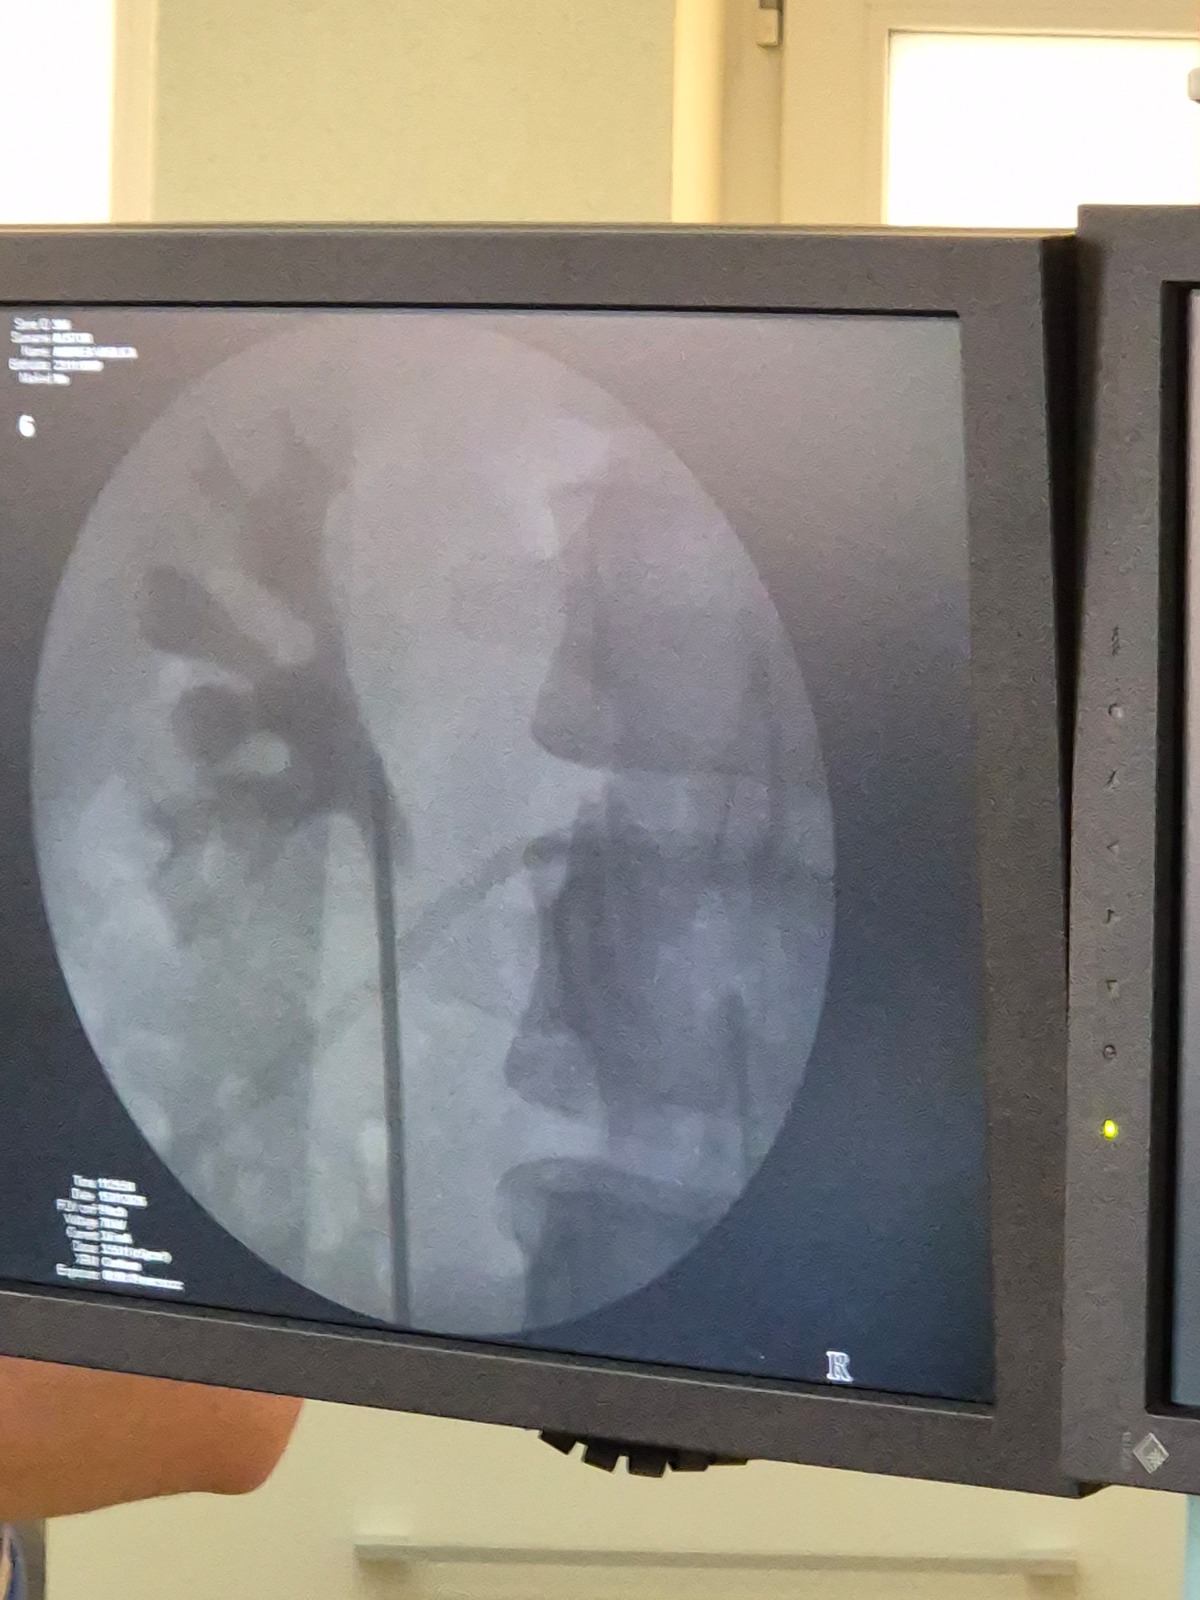

Primele patru intervenții chirurgicale au vizat pacienți diagnosticați cu litiază renală și litiază ureterală – doi bărbați și două femei – și au constat în proceduri de ureteroscopie flexibilă cu litotriție laser. Această metodă modernă permite fragmentarea calculilor renali și ureterali fără incizii chirurgicale, reducând semnificativ riscurile, durerea postoperatorie și perioada de recuperare.